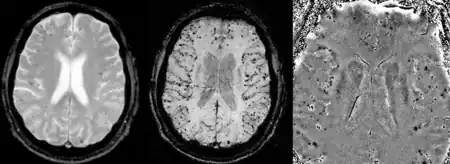

Cerebral amyloid angiopathy can be presented with lobar intracerebral hemorrhage or microbleeds in the brain. The bleeding usually occurs on the surfaces of the brain in contrast with intracranial haemorrhage due to high blood pressure which occurs in deep locations of the brain such as basal ganglia and pons. In lobar intracerebral bleed, computed tomography (CT) scan would show hyperdense haemorrhage area and hypodense odema around the haemorrhagic site.[17]

MRI sequence of gradient echo and susceptibility weighted imaging (SWI) are useful in detecting microbleeds and deposition of iron on the brain cortex (cortical superficial siderosis).[17] Other MRI indicators of CAA include white matter hyperintensities and cortical thinning.[28]